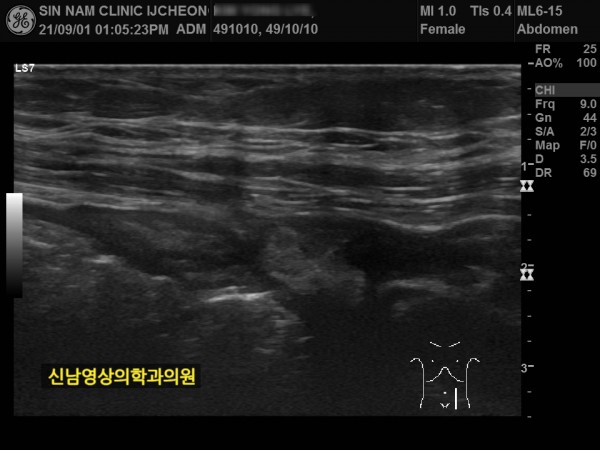

본 환자분께서는 사흘 정도 지속되는 복통과 고열로 내원하신 60대 중반의 환자분입니다.

복통 부위의 병변을 확인하기 위해서 복부 촬영과 복부 초음파검사를 진행했고, 맹장은 이상이 없고, 대장 주위로 복강삼출액(물)이 둘러싸고 있으면서 상행대장부위의 부종이 심하게 발견되었습니다.

원내 피검사상 백혈구 수치가 높아 대학병원 응급실로 전원 조치하고 응급수술을 받으셨고...

1년 뒤 수술 부위에 탈장이 발생하셔서 탈장 수술을 받으셨던 분입니다.